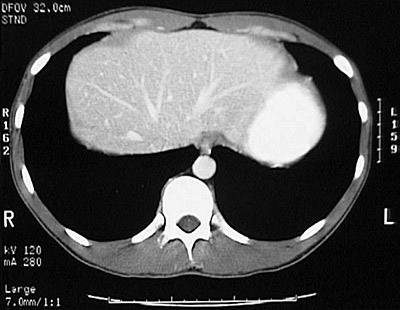

[T11] This is a normal abdominal CT scan with contrast demonstrating the liver and hepatic veins and right lung and left lung and stomach filled with contrast and esophagus and aorta in the upper abdomen.